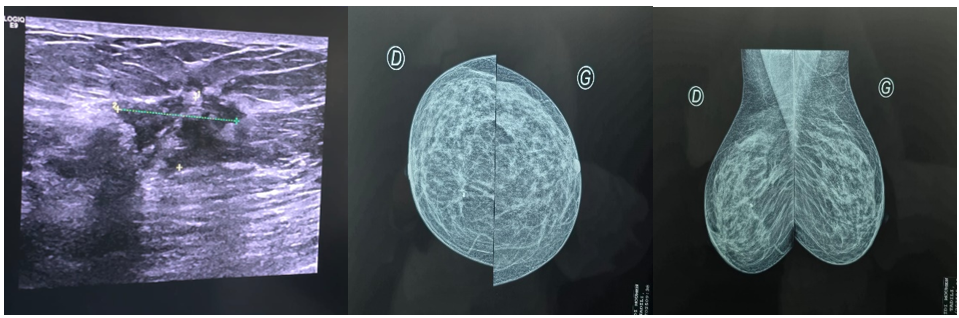

Post-chemotherapy ultrasonography showed a 14×20 mm lesion opposite the clip inserted during treatment (Figure 1).

The patient underwent a right mastectomy with axillary curage (Figure 2). Pathological analysis concluded that:

Figure 1: Ultramammography image of upper quadrant junction lesion

Figure 2: Right mastectomy specimen and axillary curage